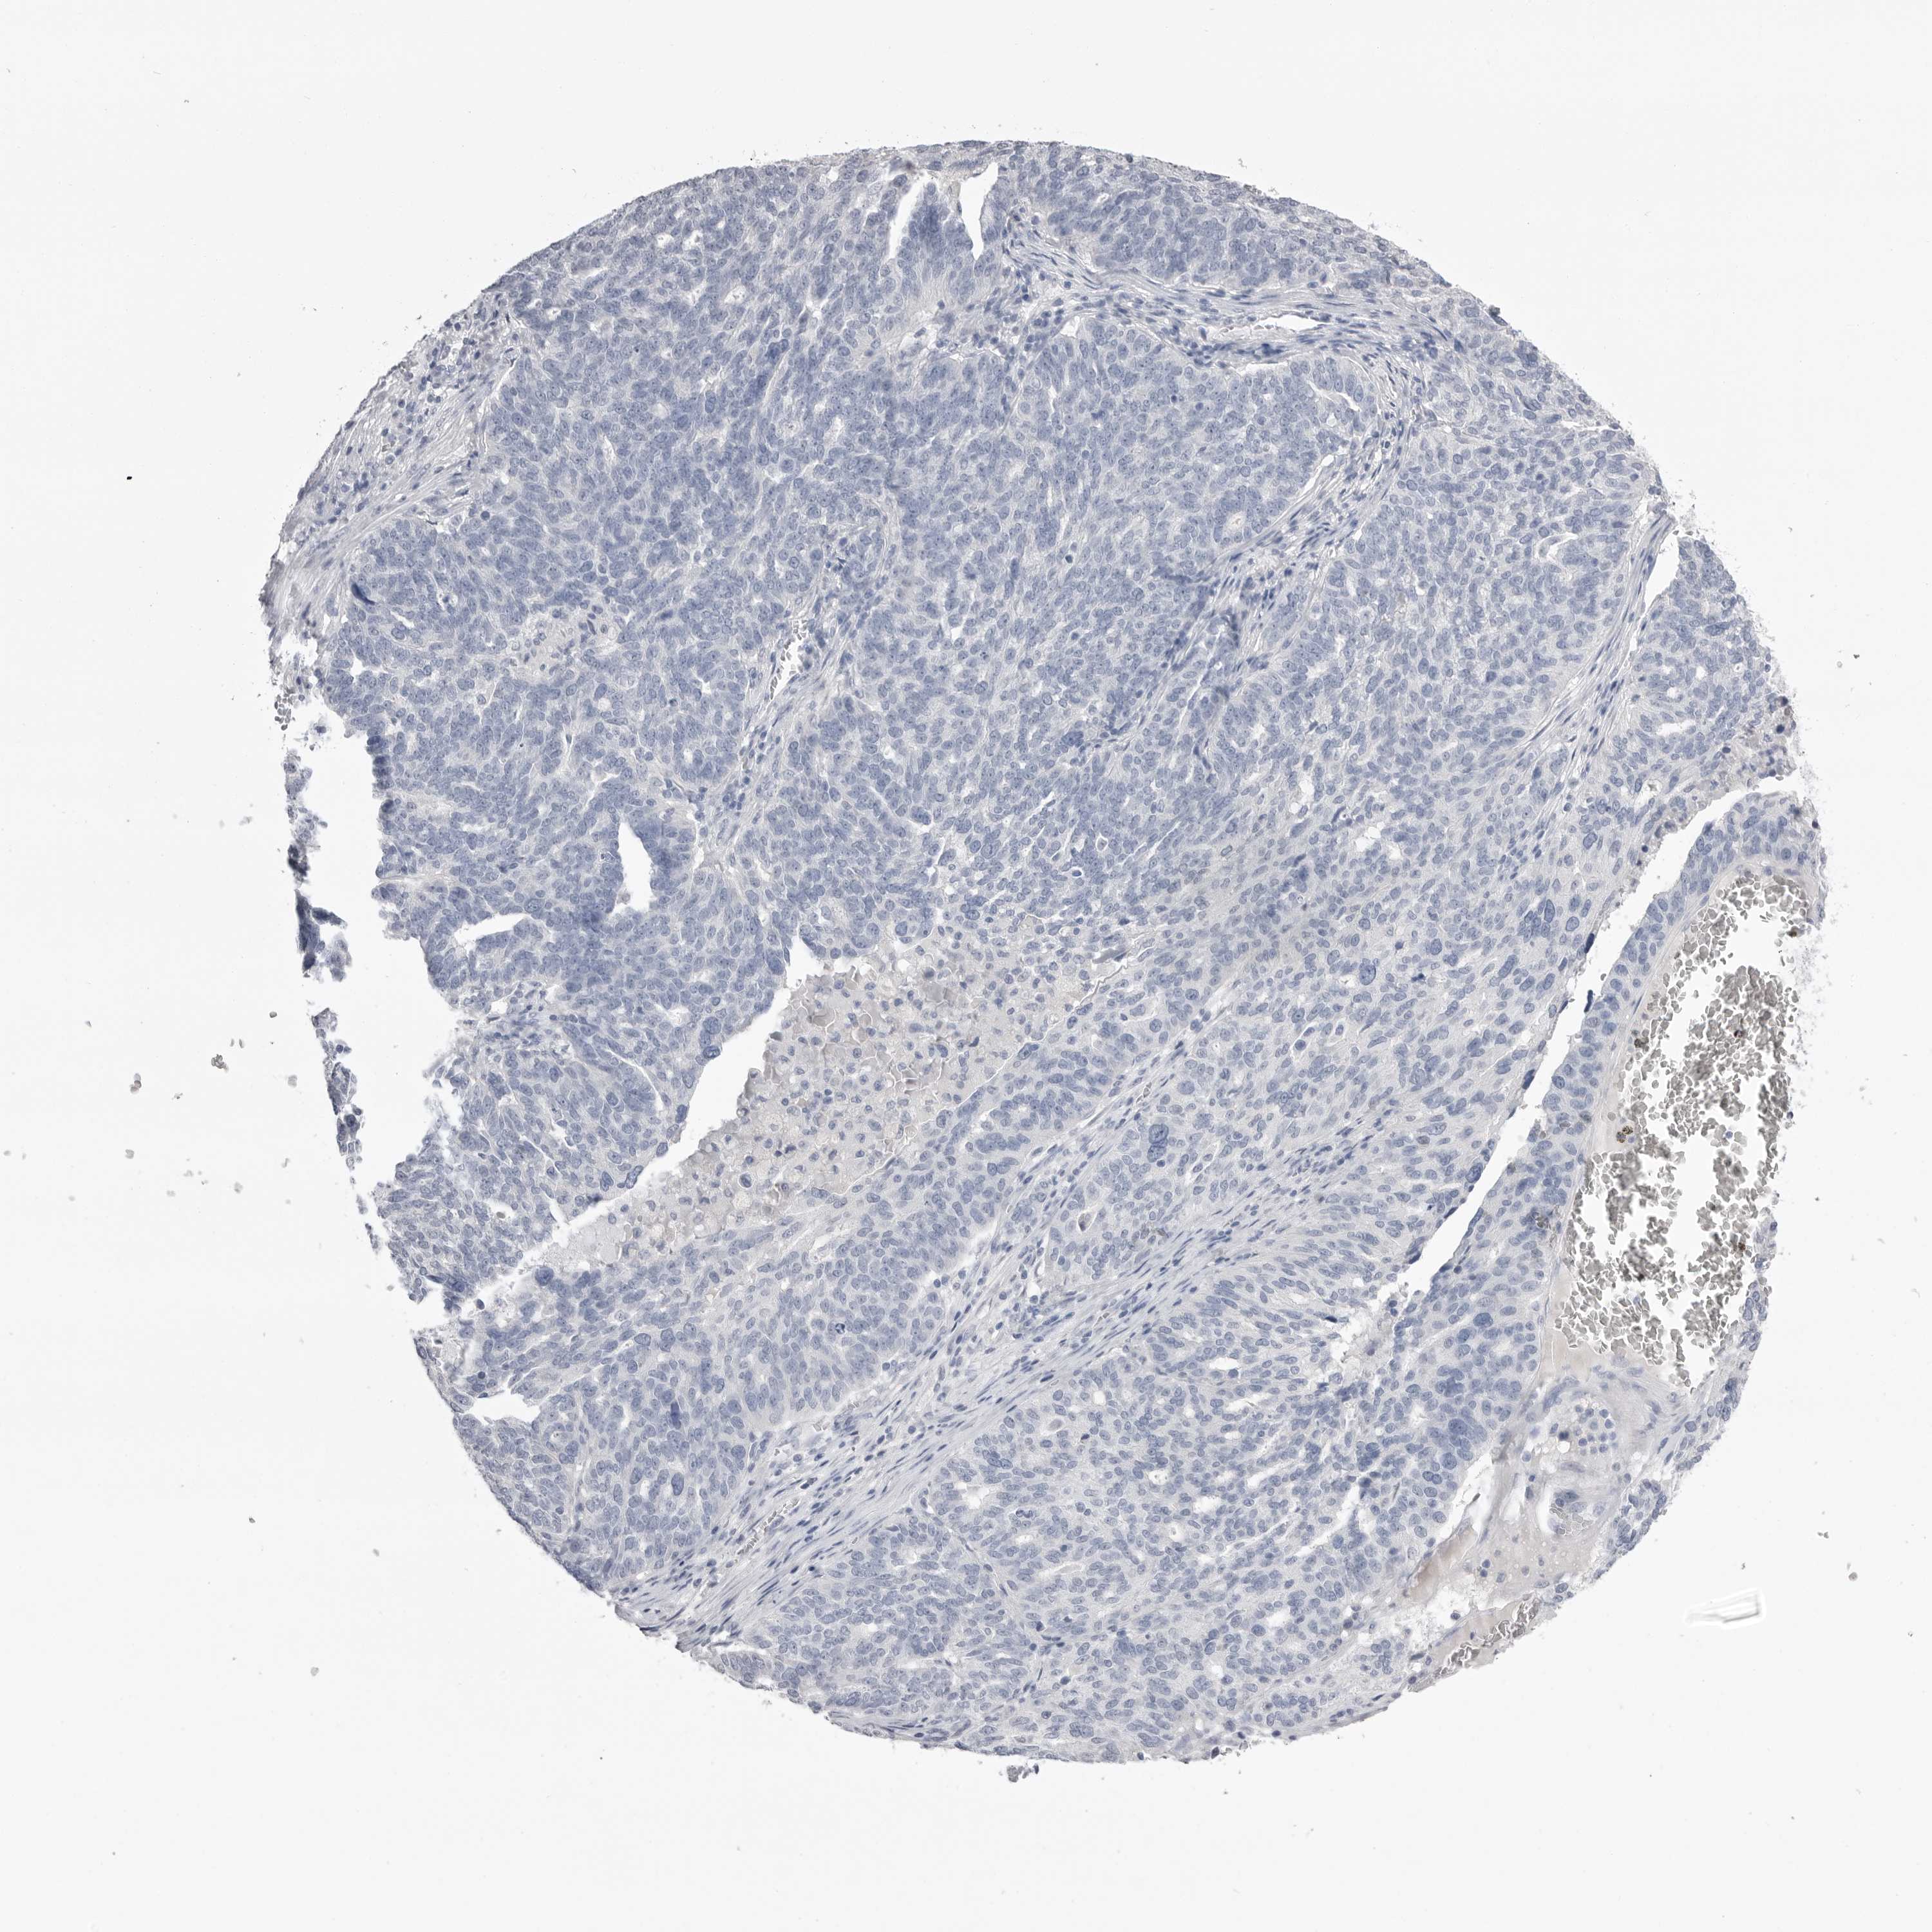

OVARIAN CANCER - Protein expressioni

A mouse-over function shows sample information and annotation data. Click on an image to view it in a full screen mode. Samples can be filtered based on level of antibody staining by selecting one or several of the following categories: high, medium, low and not detected. The assay and annotation is described here.

Note that samples used for immunohistochemistry by the Human Protein Atlas do not correspond to samples in the TCGA dataset.

Antibody stainingi

Antibody staining in the annotated cell types in the current human tissue is reported as not detected, low, medium, or high, based on conventional immunohistochemistry profiling in selected tissues. This score is based on the combination of the staining intensity and fraction of stained cells.

Each image is clickable and will lead to virtual microscopy that enables deeper exploration of all samples and also displays staining intensity scores, fraction scores and subcellular localization as well as patient and tissue information for each sample.

Antibody CAB026158